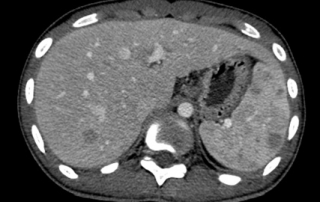

Clinique : plusieurs adénopathies cervicales droite, une adénopathie axillaire droite. Splénomégalie palpable. Présence de signes généraux, sueurs nocturnes et fièvre depuis 4 semaines, amaigrissement de 10 Kg en 4 mois. Douleurs lombaires récentes. VS 120 mm 1ère heure, hémoglobine 7,7 g/l, leucocytes 26.3 G/L, lymphocytes 1.8 G/L, albumine 28.7 g/l. Biopsie ostéo-médullaire absence d’infiltration.